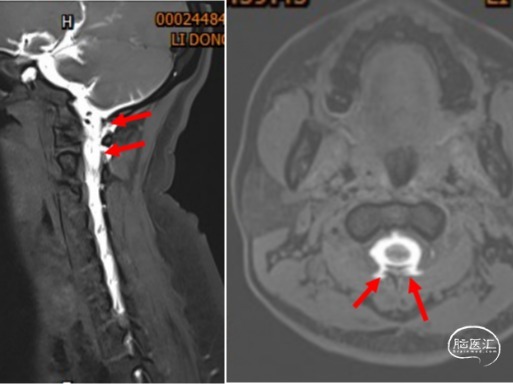

患者,女,36岁,因“头痛6天”入院于2002.5.19,入院后考虑“自发性低颅压头痛”,腰穿测压25mmH2O。行全脊髓MRI水成像未见异常,遂行全脊髓MRI造影术提示:颈1.2间左右两处瘘口分别位于颈1椎板上下缘。行DSA下精准靶向硬膜外血贴治疗后,患者第二天症状明显改善,第三天即痊愈出院。嘱患者两周后复查,因患者恢复满意,2周后患者不愿再做复查。

图2:颈髓MRI水成像未见异常。